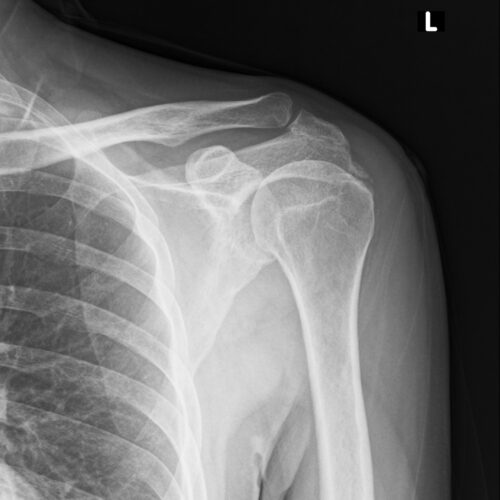

石灰沈着性肩腱板炎

51歳 男性

左肩関節の痛みが強く、一切の挙上ができないため来院。

Xp:著明な石灰化所見あり